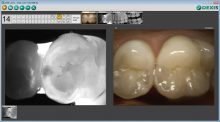

CariVu gives an impressive visual image of caries similar to an X-ray. The enamel appears transparent, and caries shows up as dark areas that are easy to see and understand. CariVu, with its broad use for occlusal, interproximal, and recurrent carious lesions and cracks, offers 99% accuracy. We use it on any patient not yet due for radiographs or who is reluctant to allow radiographs. In some cases, after we use CariVu, the patients are more willing to allow radiographs to further determine if treatment is necessary.

As part of our office technology, monitors are positioned above the patient’s head, and we can show CariVu images and explain our findings. It is easy to see the difference between the perfect tooth and a tooth with a carious lesion.